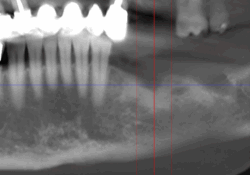

Lorsque l’os de la mâchoire est insuffisant pour soutenir un implant dentaire, des techniques de reconstruction osseuse peuvent être nécessaires. Ces procédures permettent d’augmenter le volume osseux pour garantir la stabilité de l’implant.

- Greffe osseuse : Ajout d’os ou de matériaux pour augmenter le volume osseux.

- Régénération Osseuse Guidée : Stimule la repousse osseuse grâce à des biomatériaux.

- Sinus Lift : Augmentation de l’os dans la région des molaires supérieures par élévation des sinus.